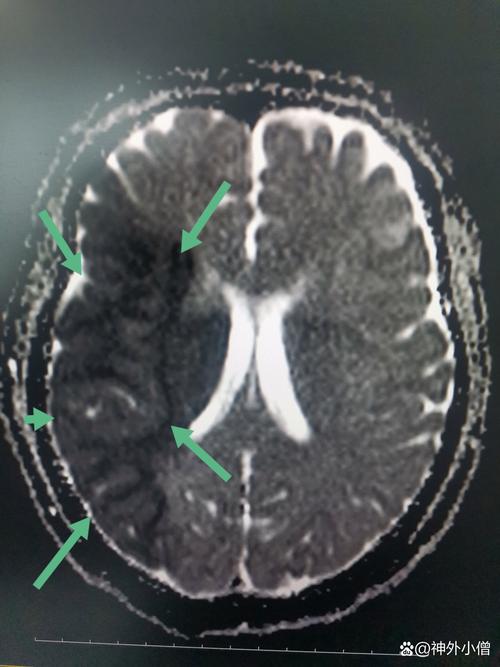

- 影像学证实:CT或MRI显示存在大血管闭塞,且脑组织尚未发生不可逆的坏死(即存在“缺血半暗带”)。